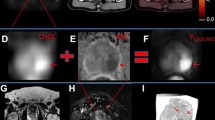

Using 68Ga PSMA-11 PET/MRI, preliminary results indicate that it might be at least equivalent to standalone multiparametric MRI for intraprostatic tumor localization (Eiber et al. 2015). Exploiting combined 68Ga-PSMA11 PET/MRI for direct comparison in 53 intermediate/high risk patients the sensitivity of mpMRI using PI-RADS criteria amounted to 43% compared to 64% for 68Ga-PSMA11 PET. Simultaneous PET/MRI, combining functional and mpMR data, further improved sensitivity to 76%. When compared to published data for mpMRI, 68Ga PSMA-11 PET/MRI shows comparable sensitivity but notably higher specificity (Eiber et al. 2015). Important application areas of 68Ga PSMA-11 PET/MRI may include precise radiation therapy planning or biopsy targeting with PET/MRI-based, ultrasound-guided or in-bore biopsy systems in order to use the improved tumor detection ability of 68Ga PSMA-11 PET/MRI in patients with previously negative prostate biopsies. Figure 4.1 gives an example of a multiparametric MR examination combined with PET in a patient with a biopsy-proven prostate carcinoma.

68Ga PSMA-11 PET/MR images from a patient with biopsy-proven Gleason 4 + 4 prostate cancer at initial staging. The images demonstrate exemplarily the combination of multi-parametric MRI with PET. The prostate harbors a large hypo-intense lesion of the left peripheral and parts of the transitional zone (a) with increased 68Ga PSMA-11 uptake (b), diffusion restriction, shown as a corresponding hypo-intensity in the ADC map (c), and pathological early enhancement in dynamic-contrast-enhanced imaging (d)

Imaging of biochemical recurrence of prostate cancer is probably the most important field of PET imaging with choline derivatives or PSMA ligands. Especially precise imaging of the prostate bed after radical prostatectomy is challenging, as this anatomical region is complex due to scar tissue and postoperative changes as well as urine collection at the urethro-urethral anastomosis. As a result of this, both MR imaging and PET imaging are limited on their own, as scar tissue might be misinterpreted as local recurrence in MRI, and a potential local recurrence might be overlooked in PET/CT due to limited soft tissue contrast. In this regard, integrated PET/MRI offers a solution, as unclear tracer accumulations in the prostate bed can be precisely assigned to anatomical structures and suspicious soft-tissue lesions. Moreover, the multiparametric approach including diffusion-weighted imaging and contrast-enhanced imaging allows for improved characterization of unclear PET positive lesions in the prostate bed (Lütje et al. 2017, Freitag et al. 2017). Figures 4.2 and 4.3 outline the additional value of mpMRI to PSMA-ligand PET and choline PET by using PET/MRI in patients with biochemical recurrent prostate cancer.

Images from integrated 68Ga PSMA-11 PET/MRI in a patient with biochemical recurrence after radical prostatectomy. PET/MRI identifies a soft-tissue lesion between the rectal and bladder wall diagnostic for local recurrence after radical prostatectomy (b–d). Due to the lack of soft-tissue contrast, it was regarded as part of the urinary bladder in PET/CT (a). Contrast-enhanced MRI demonstrates a clear soft-tissue mass (b) with68Ga PSMA-11 uptake (c) and a corresponding diffusion restriction (d)

11C-Choline PET/CT and PET/MR of a 79y/o patient with biochemical recurrence (PSA 1.7 ng/ml) after radical prostatectomy (upper row). PET/CT showed a faint choline uptake adjacent to the bladder on the left side which raised the suspicion for local recurrence but was judged as being unclear. PET/MR images demonstrated tracer uptake in a tiny tissue nodule (middle row). Additional information from the functional MR sequences showed a diffusion restriction in the ADC map (left, lower row). The iAUC60 derived from DCE (middle, lower row) and its fusion with T2w (right, lower row) demonstrated intense early contrast media influx. In conjunction with the choline uptake, the findings from functional MRI were highly indicative for a local recurrence